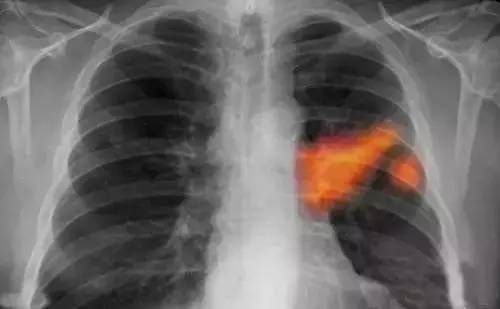

武漢肺癌最新動態(tài)顯示,研究、治療和科普工作取得重要進(jìn)展。當(dāng)?shù)蒯t(yī)療機(jī)構(gòu)和專家團(tuán)隊(duì)不斷深入研究肺癌的發(fā)病機(jī)制,采用最新的治療技術(shù),提高患者生存率。科普宣傳也加強(qiáng),提高公眾對肺癌的認(rèn)識,促進(jìn)早期發(fā)現(xiàn)和治療。這些努力為肺癌患者帶來希望,展示了武漢在肺癌領(lǐng)域的積極進(jìn)展。

武漢的科研團(tuán)隊(duì)在肺癌的基因組學(xué)研究方面取得了重要突破,某研究團(tuán)隊(duì)成功識別了數(shù)個(gè)與肺癌發(fā)生、發(fā)展密切相關(guān)的關(guān)鍵基因,這一發(fā)現(xiàn)為肺癌的精準(zhǔn)治療提供了有力支持,該團(tuán)隊(duì)還積極參與臨床試驗(yàn)和新藥研發(fā),與制藥公司緊密合作,推動多項(xiàng)針對肺癌的新藥進(jìn)入臨床試驗(yàn)階段,部分新藥已顯示出顯著的療效,為肺癌患者帶來了新的希望。

武漢肺癌治療進(jìn)展

在手術(shù)治療方面,武漢的醫(yī)療機(jī)構(gòu)引入了先進(jìn)的手術(shù)設(shè)備和技術(shù),如機(jī)器人手術(shù)系統(tǒng),通過這一技術(shù),醫(yī)生和醫(yī)療團(tuán)隊(duì)能夠更精準(zhǔn)、更安全地進(jìn)行肺癌手術(shù),大大提升了手術(shù)成功率,針對肺癌的綜合治療,武漢的專家團(tuán)隊(duì)積極優(yōu)化治療方案,結(jié)合患者的具體情況,采用免疫治療、靶向治療等新型治療方法,為患者提供更加個(gè)性化的治療方案,某肺癌患者經(jīng)過綜合治療,成功戰(zhàn)勝病魔的案例便是其中的亮點(diǎn)。